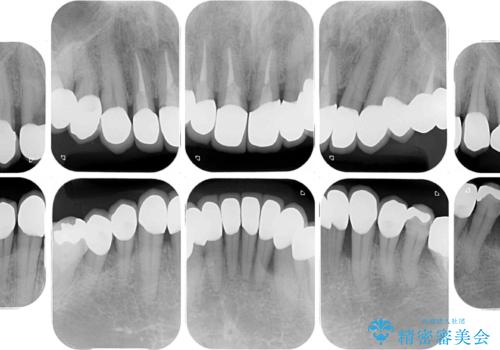

- 幼少期の薬剤の影響で歯が変色していていることを気にして来院された患者様です。

仕事も落ち着き、長年気にしていた前歯の色をきれいにしたいとのことでした。

上下ともに前歯のセラミッククラウンによる補綴治療を希望されていましたが、下顎前歯は叢生が強いため、補綴治療前に部分矯正を行って歯列を整えた上で、補綴治療を行うこととしました。

臼歯部には歯周ポケットのある箇所が散見されましたが、まずは前歯を治療したいとのことで、治療を進めました。